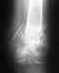

Здравствуйте уважаемые доктора! 18.01.2009 каталась на коньках, сломала ногу. У меня закрытый перелом костей н/3 правой голени со смещением обоих костей. 30.01.09 г. сделали операцию, остеосинтез штырем и 4 винтами, до этого находилась на скелетном вытяжение за пяточную кость. После снятия швов, надели лангет без закрытия пальцев до колена. 13.03.09 г. под м/а выполнено удаление 2 винтов, разрешена дозированная нагрузка (наступаю на костылях в лангете, функция суставов практически без ограничений). До операции врачи говорили, что в ранние сроки смогу приступить к полноценной жизни, прошло больше 3 месяцев со дня операции но возвращение к полноценной жизни так и не произошло. Последний снимок сделала 24.04.09 г., посмотрев снимки врач сказал, что консолидация перелома слабая и рекомендовал еще 1 месяц до следующего снимка продолжать ходить на костылях с дозированной нагрузкой.Меня беспокоят снимки, кости сопоставлены не совсем ровно (это только мое мнение, не знаю как должно быть). Почему так долго не срастается перелом, сроки срастания с таким диагнозом? Когда начинать бить тревогу? Что можно сделать, что бы ускорить процесс заживления?- Мне 22 года- Не курю, ни каких заболеваний нету- Принимаю кальций Д3 Никомед, МУМИЕ, хорошее питаниеБуду рада получить от Вас любую полезную информацию.Заранее благодарю всех тех, кто со вниманием отнесется к моей проблеме.

По снимкам - несостоятельный остеосинтез. Нижний отломок большеберцовой кости стержень не удерживает, тем более и винтов в нем нет. Есть неустраненное значительное смещение. Возможно, стержень уже сломан (есть его деформация).

Остеосинтез надо переделать, стержень взять потолще и ввести поглубже, устранив попутно все смещения, и запереть в нижнем отломке 3 винтами. Кальций Д3 не нужен, мумие вообще нонсенс (XXI век на дворе!).